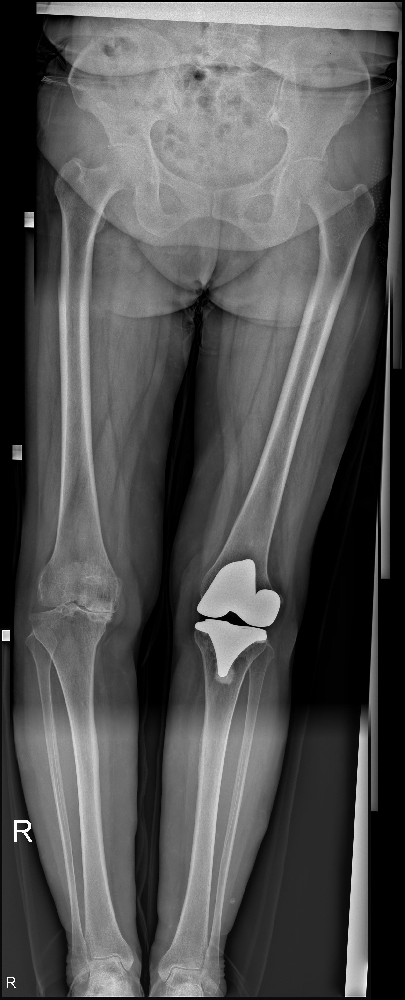

終于,在被送往市中區(qū)誠德骨科醫(yī)院接受進(jìn)一步檢查后,張廣美接受了雙側(cè)全膝關(guān)節(jié)置換手術(shù),并且術(shù)后的恢復(fù)效果非常良好。

雙側(cè)全膝關(guān)節(jié)置換手術(shù)是一種常見的治療方法,主要是通過將病變的膝關(guān)節(jié)組織替換為人工關(guān)節(jié)來改善患者的運(yùn)動(dòng)功能和減輕關(guān)節(jié)疼痛。這種手術(shù)旨在重建膝關(guān)節(jié)的穩(wěn)定性和功能,提高患者的生活質(zhì)量。